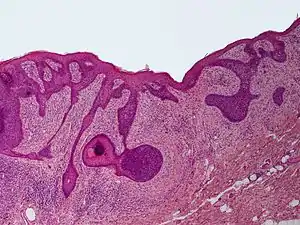

Perifollicular fibroma

Perifollicular fibroma is a cutaneous condition, a benign tumor usually skin colored, most often affecting the face and upper trunk.[1]: 674 [2]